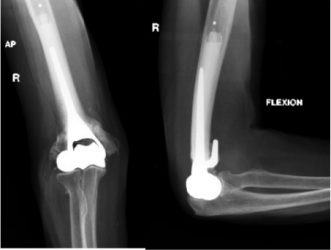

Appearance after hemiarthroplasty